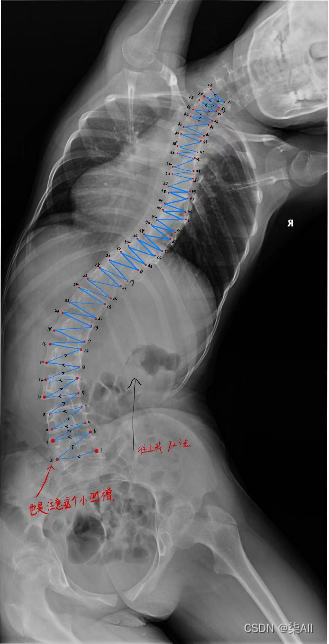

2、开始标注(以冠状位为例,其他方位是一样的操作,视频教程)

冠状位关键点标注教程

3、冠状位标注结果

4、标注过程注意事项

5、标注结果注意

(0) 最后一个椎体看不清的话,最后一个肋骨连接的就是胸12 也就是T 12 ,下面那个就是L1(腰椎1),往下数五个就是 最后一个腰椎

(3)像这种椎骨不要变化太大,一般都是底下的椎骨大一些,往上逐渐减少,就因为看不清,所以得这样表

还是有很多问题的,这种计算cobb角肯定有问题,最后一个椎骨看不清,那画的线就与上一个椎骨平行,尽量平行标,要不然后面自动生成cobb角,误差很大,这样肯定不行,注意一下,认真一些,要不然得返修几次,不如好好弄,还节省时间

###(5) 参考AASCE2019 GT图